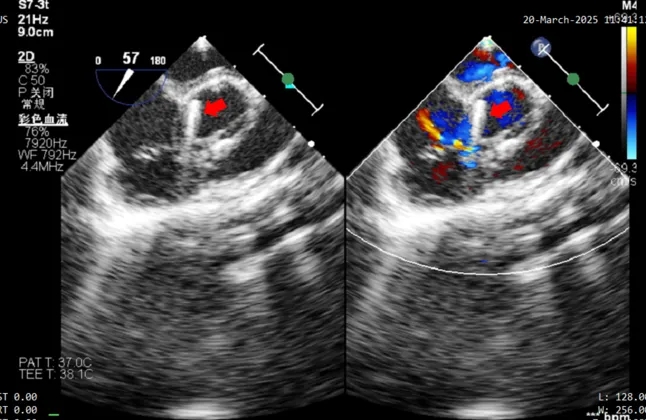

术中超声复测

膨出瘤基底部宽约7.6mm

两处破口分别宽约2.3mm及1.3mm